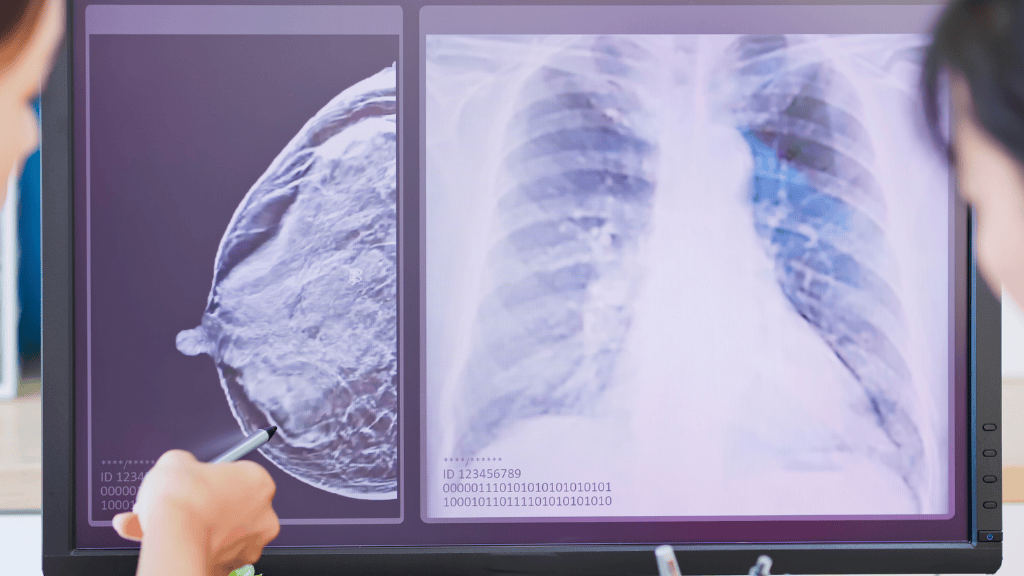

Breast cancer remains the most commonly diagnosed cancer among women worldwide. Early detection through regular mammography screening is one of the most effective strategies to reduce mortality. Now, large-scale clinical evidence confirms that artificial intelligence (AI) can significantly enhance this process.

A recent clinical trial published in The Lancet, involving more than 100,000 women has shown that AI-supported mammography improves early breast cancer detection rates while maintaining safety standards and reducing radiologist workload. These findings mark a turning point in how screening programs may be structured in the coming years.

The MASAI trial, a large, prospective, randomised clinical study conducted in a real-world population screening programme, included more than 100,000 women and compared AI-supported mammography with traditional double reading by two independent radiologists.

As explained by Ignacio Miranda Gómez, Head of the Breast Imaging Unit at the International Breast Cancer Center IBCC and Teknon Medical Center, the trial goes beyond simply detecting more cancers. It demonstrates that AI contributes to identifying tumours earlier and with more favourable biological characteristics, likely due to improved detection of subtle lesions that can be difficult to interpret with the human eye alone.